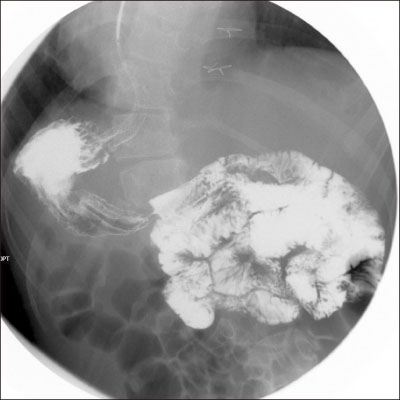

During laparoscopic exploration, adhesion of the transverse colon to the stomach wall of the gastrostomy site was seen and appeared twisted (

Fig. 3). Proximal transverse colon was redundant and upstream dilatation from the twisted transverse colon to the ascending colon and the cecum was found with reversed intestinal anatomy, as identified on preoperative images. Sigmoid colon was collapsed and not redundant, so the suspicious sites of endoscopy were not related to the symptoms. Adhesiolysis and fibrous band lysis between the transverse colon and adherent soft tissue was done. Redundant proximal transverse colon was resected via mini-laparotomy site, and end-to-end colocolic anastomosis was performed (

Fig. 3Adhesion of transverse colon on stomach wall and twisting (arrow) with upstream colon dilatation (arrowhead).